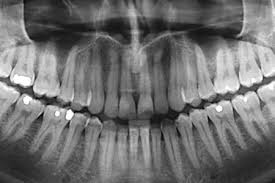

Dental X-Rays are generally safe and the amount of radiation used is very low. Dentist is only take X-Ray when necessary for diagnosing or monitoring oral health.